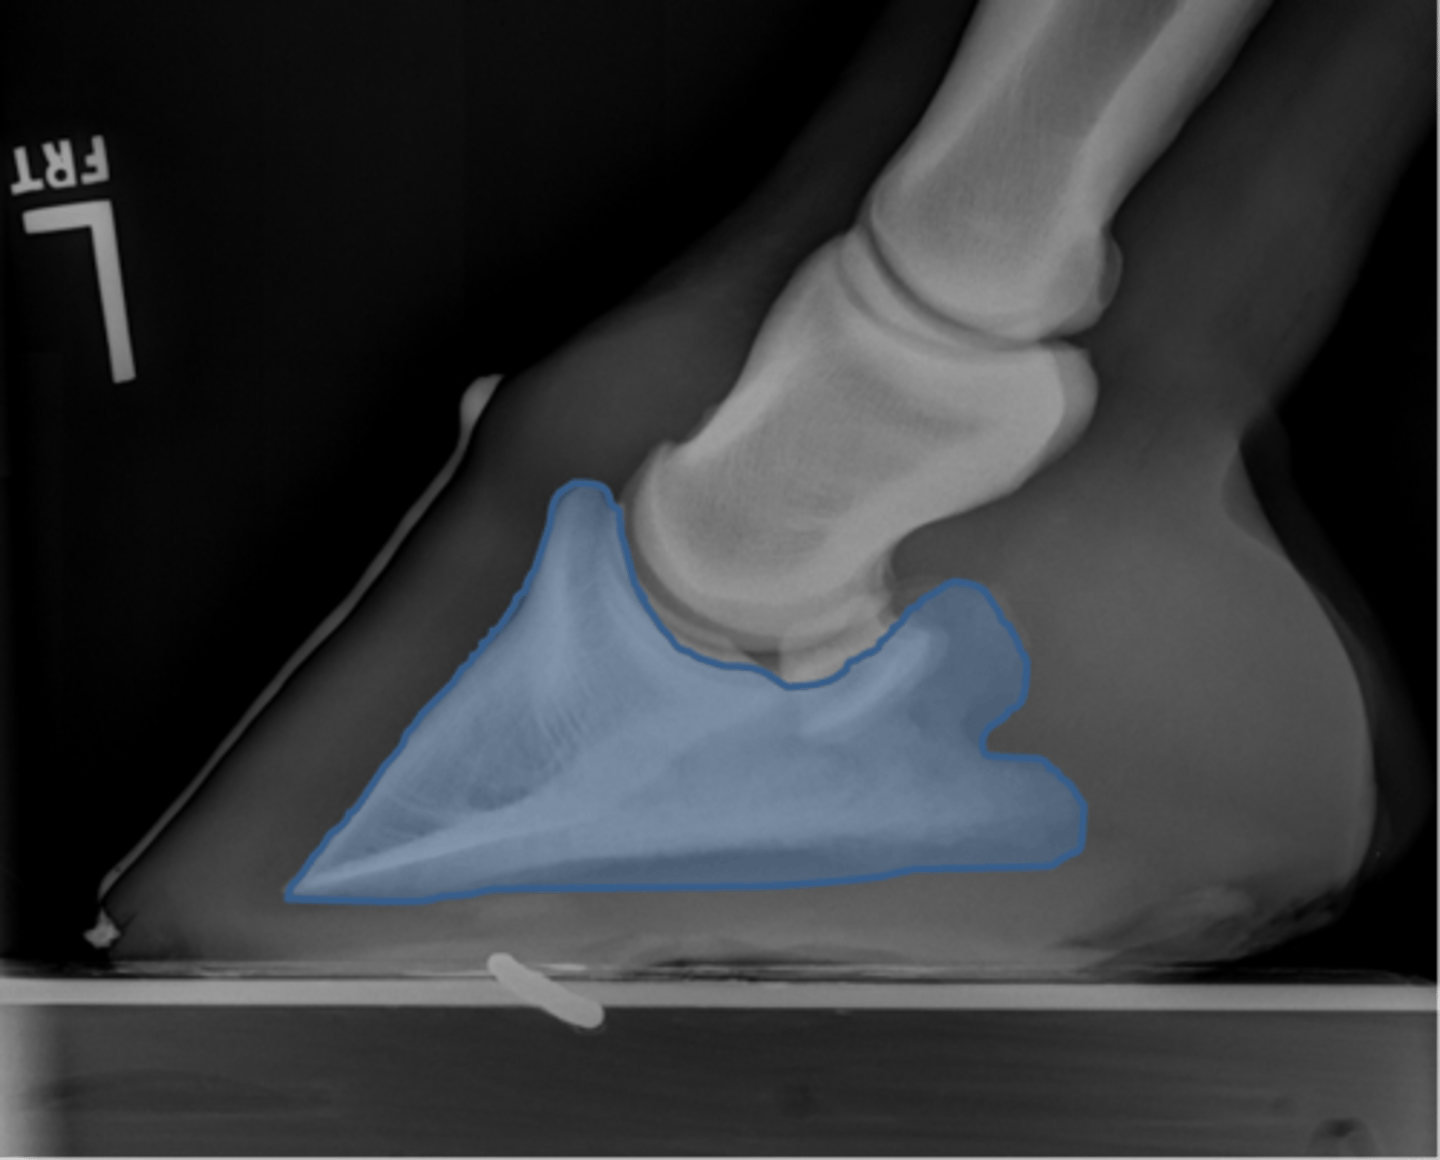

Coffin bone (P3)

Navicular bone

Coffin joint

Short pastern (P2)

What view is this?

Coffin bone

Navicular bone

Pastern joint, LM

ID joint and view

Pastern joint, DP

ID joint and view